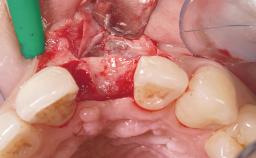

Immediate Flapless Placement of an Implant in a Maxillary Left Central Incisor Site

A 42-year-old female patient was referred to our clinic at the School of Dentistry of the University of São Paulo in November 2004, presenting a deficient restoration in the upper left central incisor. The clinical examination revealed no gingival retraction or any signs of gingival inflammation and, therefore, previous periodontal treatment was not considered. The patient presented a high lip line at full smile and a thin tissue biotype. This combination characterized a high-risk situation from an anatomic point of view, which required careful preoperative planning and cautious surgical execution.

Placement Protocol Immediate implant placement

Tooth Site Maxillary incisor or canine